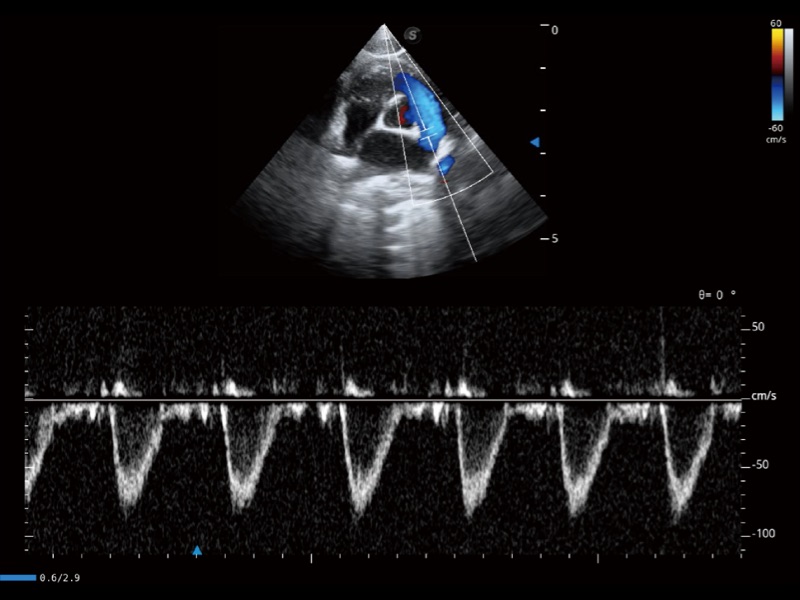

通过360度任意调节3条M型取样线,在同一心动周期上观察心脏不同位置的运动曲线,得到准确的心功能测量数据,有效评估心肌运动及左心室功能。

能够基于左心室壁追踪和辛普森法,自动计算射血分数,支持多个可移动点描迹,与手动测量相比,极大节省了动物医生的时间和精力。

实时用颜色表示心肌组织运动,观察和定量组织的运动情况,对快速检测与评估心肌的灌注和活性、电传导及心肌收缩和舒张功能等均能提供重要的诊断信息。

当心脏测量结果超出正常范围时,可实时预警提示动物医生,减少疾病漏诊概率。